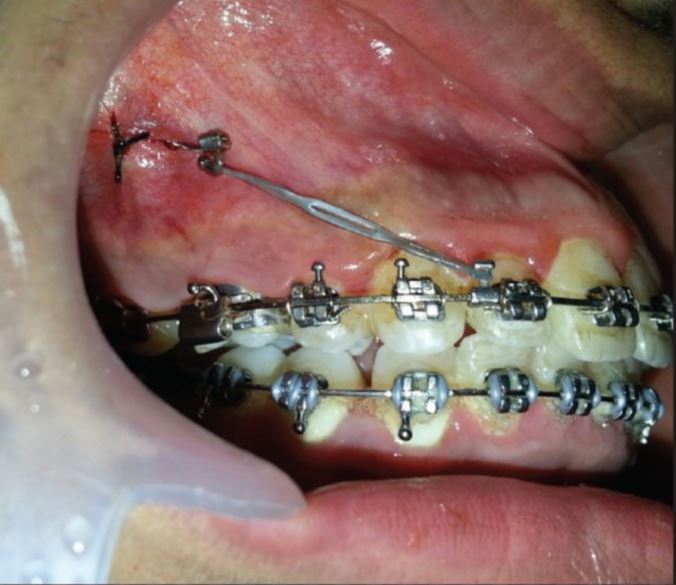

Crimpable Hooks – Curved long (Pack of 10)

- Easily crimps to arch wires

- Smooth for patient comfort

- Long hook for easy ligation